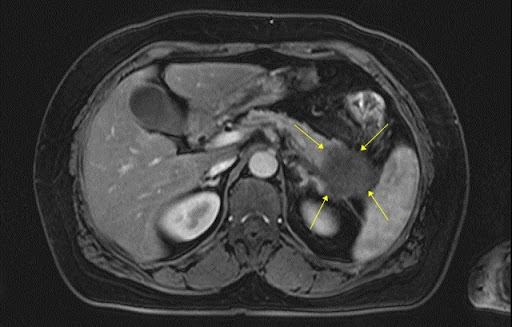

🔹 간 질환 – 지방간, 간경화, 간암 등 확인 가능

🔹 췌장염·췌장암 – 췌장에 염증이 생기거나 종양이 있는지 체크 가능

🎗 간암, 췌장암, 대장암, 신장암 등 초기 단계에서 발견 가능!

🎗 양성종양 or 악성종양(암) 판별 – 혹이 생겼다면 악성인지 양성인지 확인할 수 있음